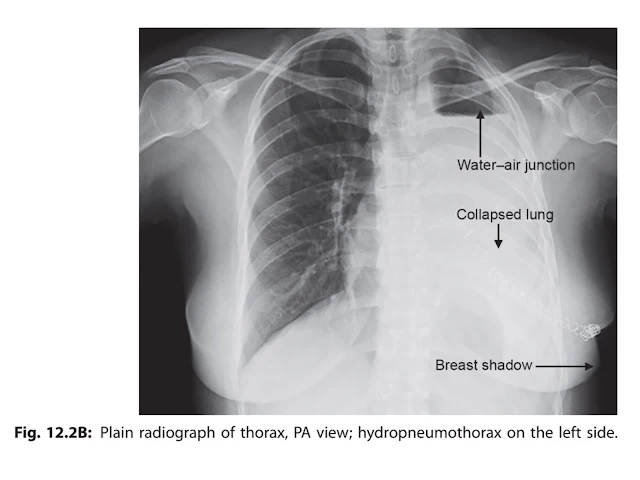

- X-Rays of Thorax